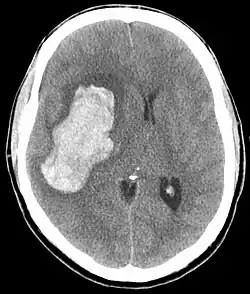

| CT scan depicting intracranial hemorrhage, a possible complication of hypertensive emergency. Patients with spontaneous intracranial hemorrhage present with newfound headache and neurologic deficits. | |